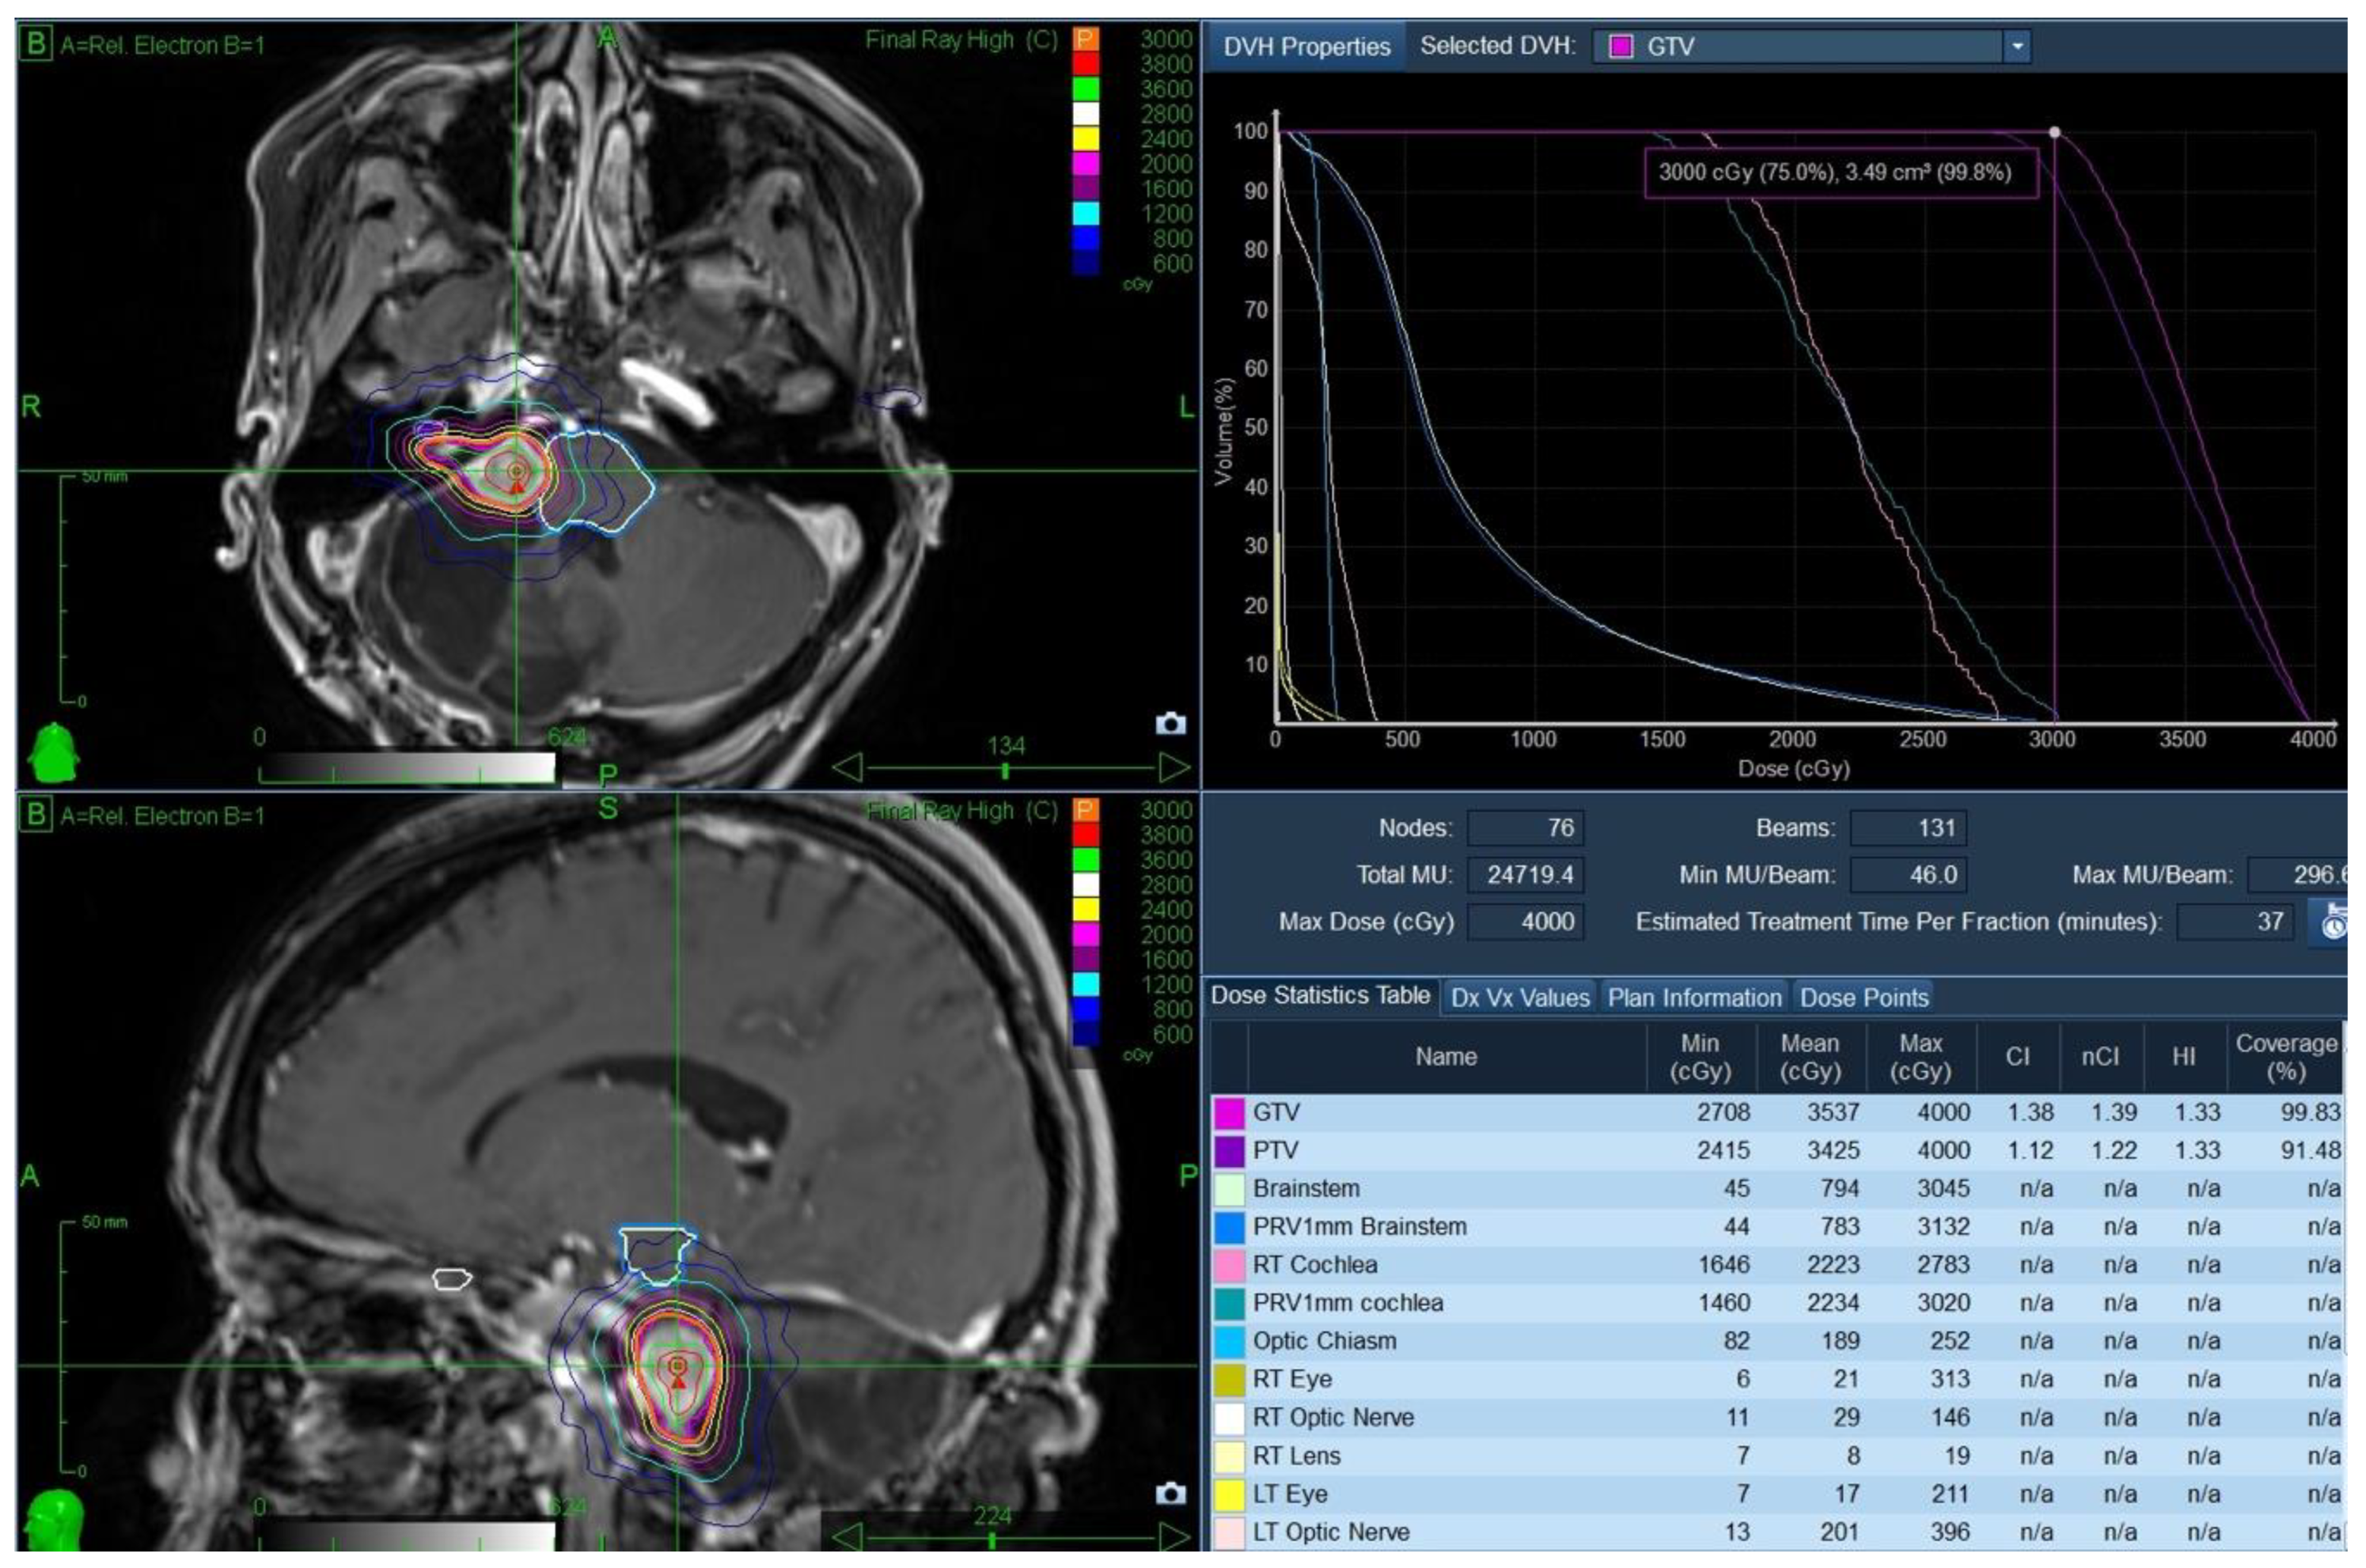

The case was discussed at neuro-oncology rounds. The multidisciplinary consensus was to offer the patient a course of stereotactic radiosurgery (SRS) using the frameless CyberKnife® (CK) as a non-invasive method of tumour control while allowing function preservation. The patient underwent CT/MR simulation and received treatment in January 2016. The gross tumour volume (GTV) was 3.5 cc and was treated to 3000 cGy in 5 fractions (GTV covered by the 99.8% isodose line), with no treatment margin. Treatment was delivered in five daily fractions over one week. A planning target volume was strictly used for treatment planning purposes. The brainstem doses were as follows: Dmax was 3045 cGy, D0.03cc was 2942 cGy, and the D1cc was 2157 cGy (Figure 4).

Figure 4. CK SRS treatment plan (January 2016) with the axial and coronal sections, the dose–volume histogram (DVH) and the dose statistics table of the pertinent volumes.